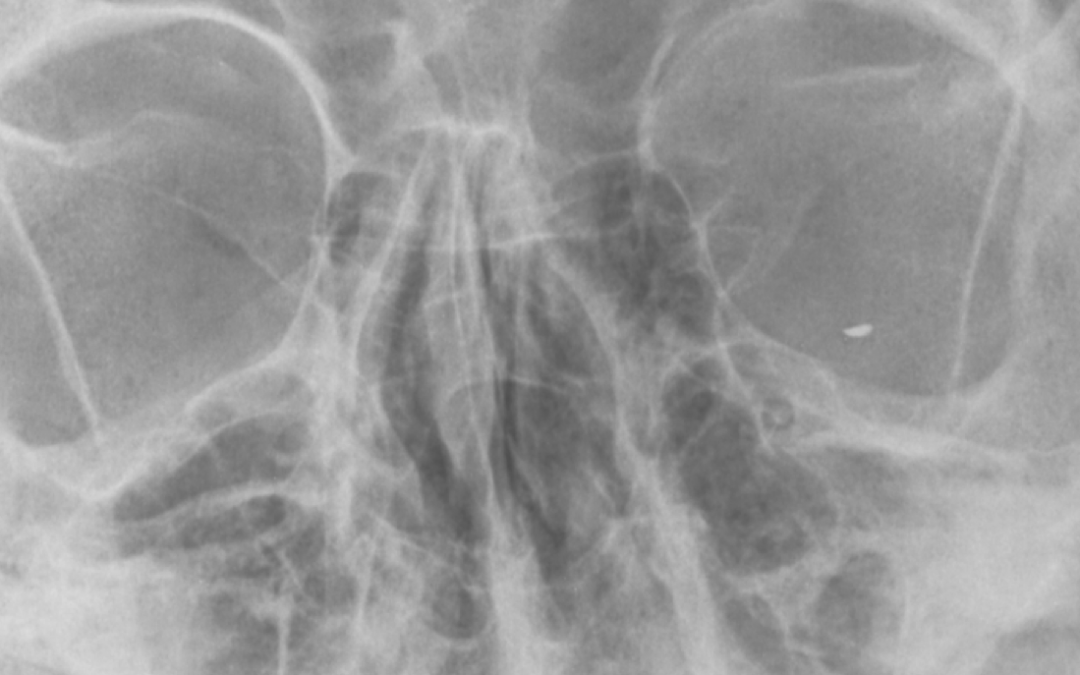

Please be careful doing DIY jobs during “lockdown”.  We have more time available and there are plenty of jobs in the house and around the garden that need fixing.  Today I have removed a small fragment of metal called an “intraocular foreign body” from the back of an...